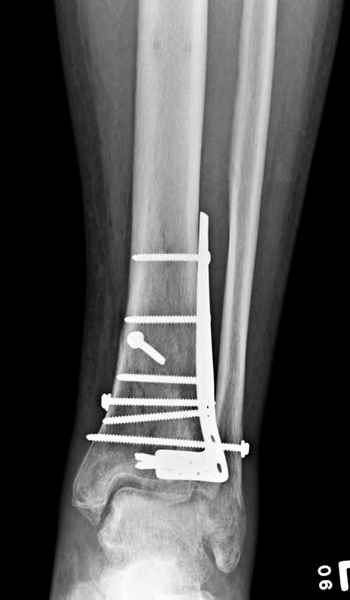

Публикации за последние пять лет показывают, что в лечении переломов пилона важным является состояние

мягких тканей. Поэтому при лечении пилона, особенно после высокоэнергетической травмы, необходимо придерживаться правила - лучше проводить запоздалую фиксацию, чем после операции иметь проблемы с мягкоткаными осложнениями.

Закрытый метод фиксации рекомендуется, когда фрагменты были сопоставлены в результате лигаментотаксиса, а открытый минимальный метод при нерепонированных отломках.

После репозиции сустава необходимо удостовериться

в заполнении образовавшейся полости ауто- или синтетическими заполнителями, что в последующем предохраняет от варусного коллапса.

После ExFix проведение компьютерной томографии считаем обязательным, получаем информацию о расположении крупных фрагментов, которая подскажет сторону операционного доступа и направления проведения фиксирующего материала.

Фиксация наружной лодыжки подсказывается переломом, а малоберцовая является ключом-ориентиром для длины конечности.

Любая фиксация - преконтурированные пластины с уголовой стабильностью, медиальная, латеральная в зависимости от нахождения отломков или наружная фиксация типа аппарата Илизарова подходят для ранней мобилизации.

Не все переломы пилона фиксируются медиальной

пластиной, поэтому, учитывая что большой фрагмент

находится на латеральной стороне, я бы применил

передне-латеральную пластину.